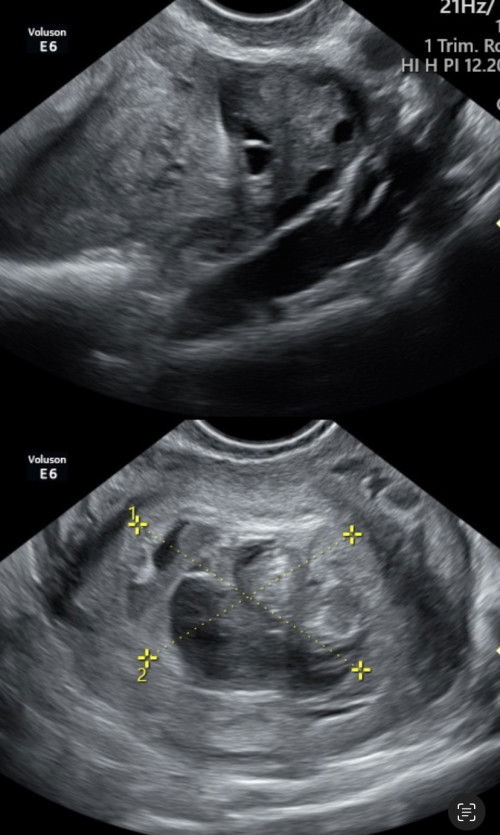

ada yg pernah ngalamin seperti ini?

sebelumnya hasil usg 5 week bagus, udah ada kantung dan rahim bersih.. setelah usg 6 week 5 day mau cek detak jantung, qodarullah.. hasil usg seperti ini, sedihnya kata dokter "kehamilannya tidak bisa di lanjut krn bermasalah" gatau penyebabnya apa(?) gak ada keluhan apapun